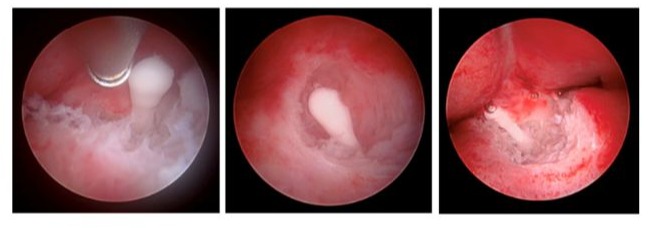

Next, we introduced the MyoSure Reach device into the cavity. Using the device’s tip, we palpated the posterior uterine wall where the IUD strings were seen prior to detachment. To precisely locate the IUD, portable X-ray imaging was performed with the MyoSure device in place to serve as a reference point.

We then systematically excised endometrial tissue at the radiographic site of the IUD, taking multiple X-ray images throughout the dissection to confirm the accurate location of the IUD in reference to the MyoSure instrument and to ensure precise dissection planes. Once a portion of the IUD was exposed, we carefully resected the surrounding tissue to liberate a significant part of the device. Hysteroscopic forceps were used to completely remove the IUD. It was found to be lying parallel to the uterine wall, requiring a larger area of exposure to achieve adequate traction for removal. Notably, we injected vasopressin into the myometrium with a hysteroscopic needle to decrease blood loss during dissection (Figures 1-5).

Figure 3: X-ray imaging guiding the initial dissection point of the MyoSure device along the posterior wall of the uterine cavity.

Figure 4: Hysteroscopic resection of the embedded IUD using the MyoSure device, following confirmation of its location with X-ray.

Figure 5: The entire Mirena IUD (without strings) following hysteroscopic endometrial dissection.